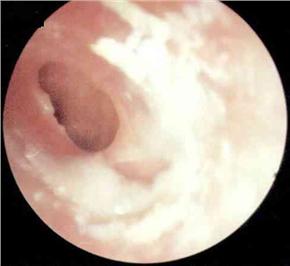

中耳炎病理图